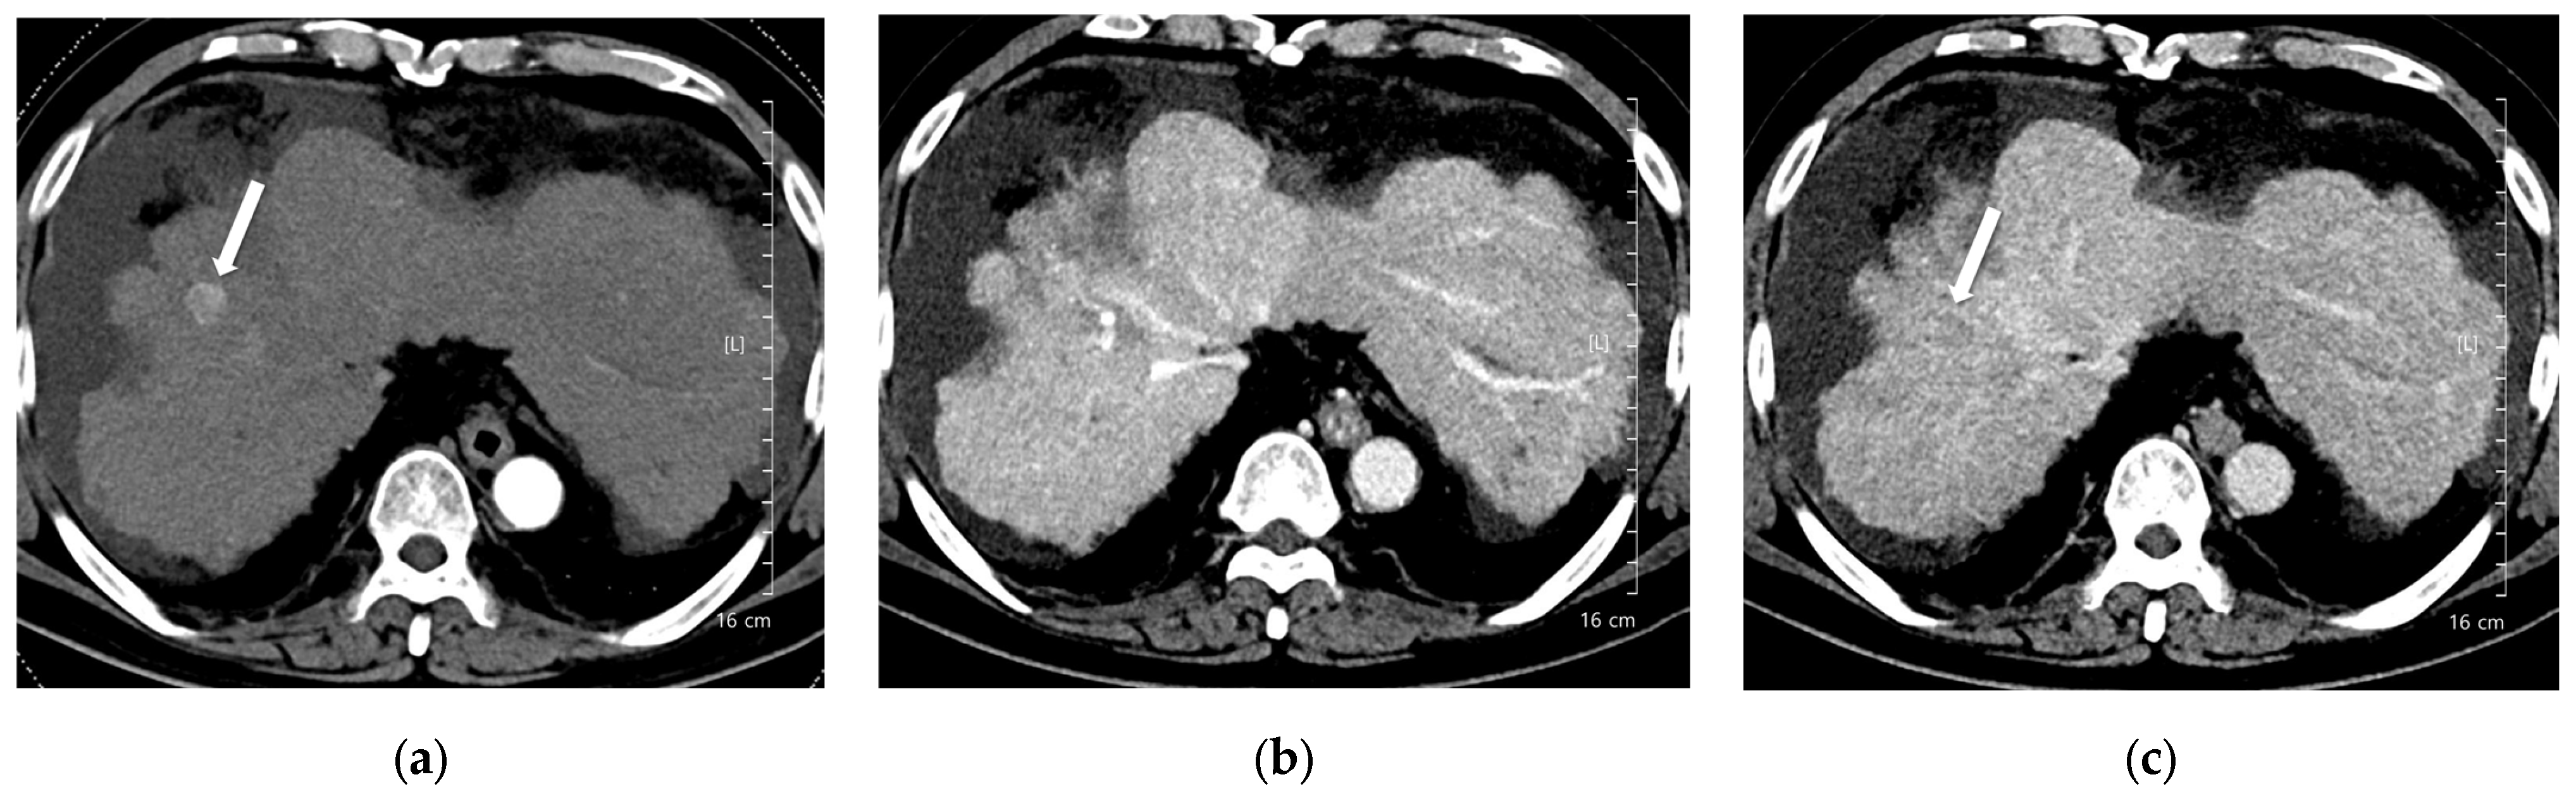

Figure 5. A 56-year-old man with hepatocellular carcinoma (HCC). CT was performed using low-concentration iodine contrast material (total iodine dose, 389.89 mg I/kg). Overall image quality in the arterial and portal phases was unacceptable (mean scores < 4): (a) A 17-mm enhancing nodule (arrow) is visible on the arterial phase at 120 kVp; (b) The nodule shows subtle washout on the portal phase (arrow); (c) The nodule is inconspicuous on the delayed phase. The two readers classified the lesion as LI-RADS 4 and LI-RADS 3, respectively.